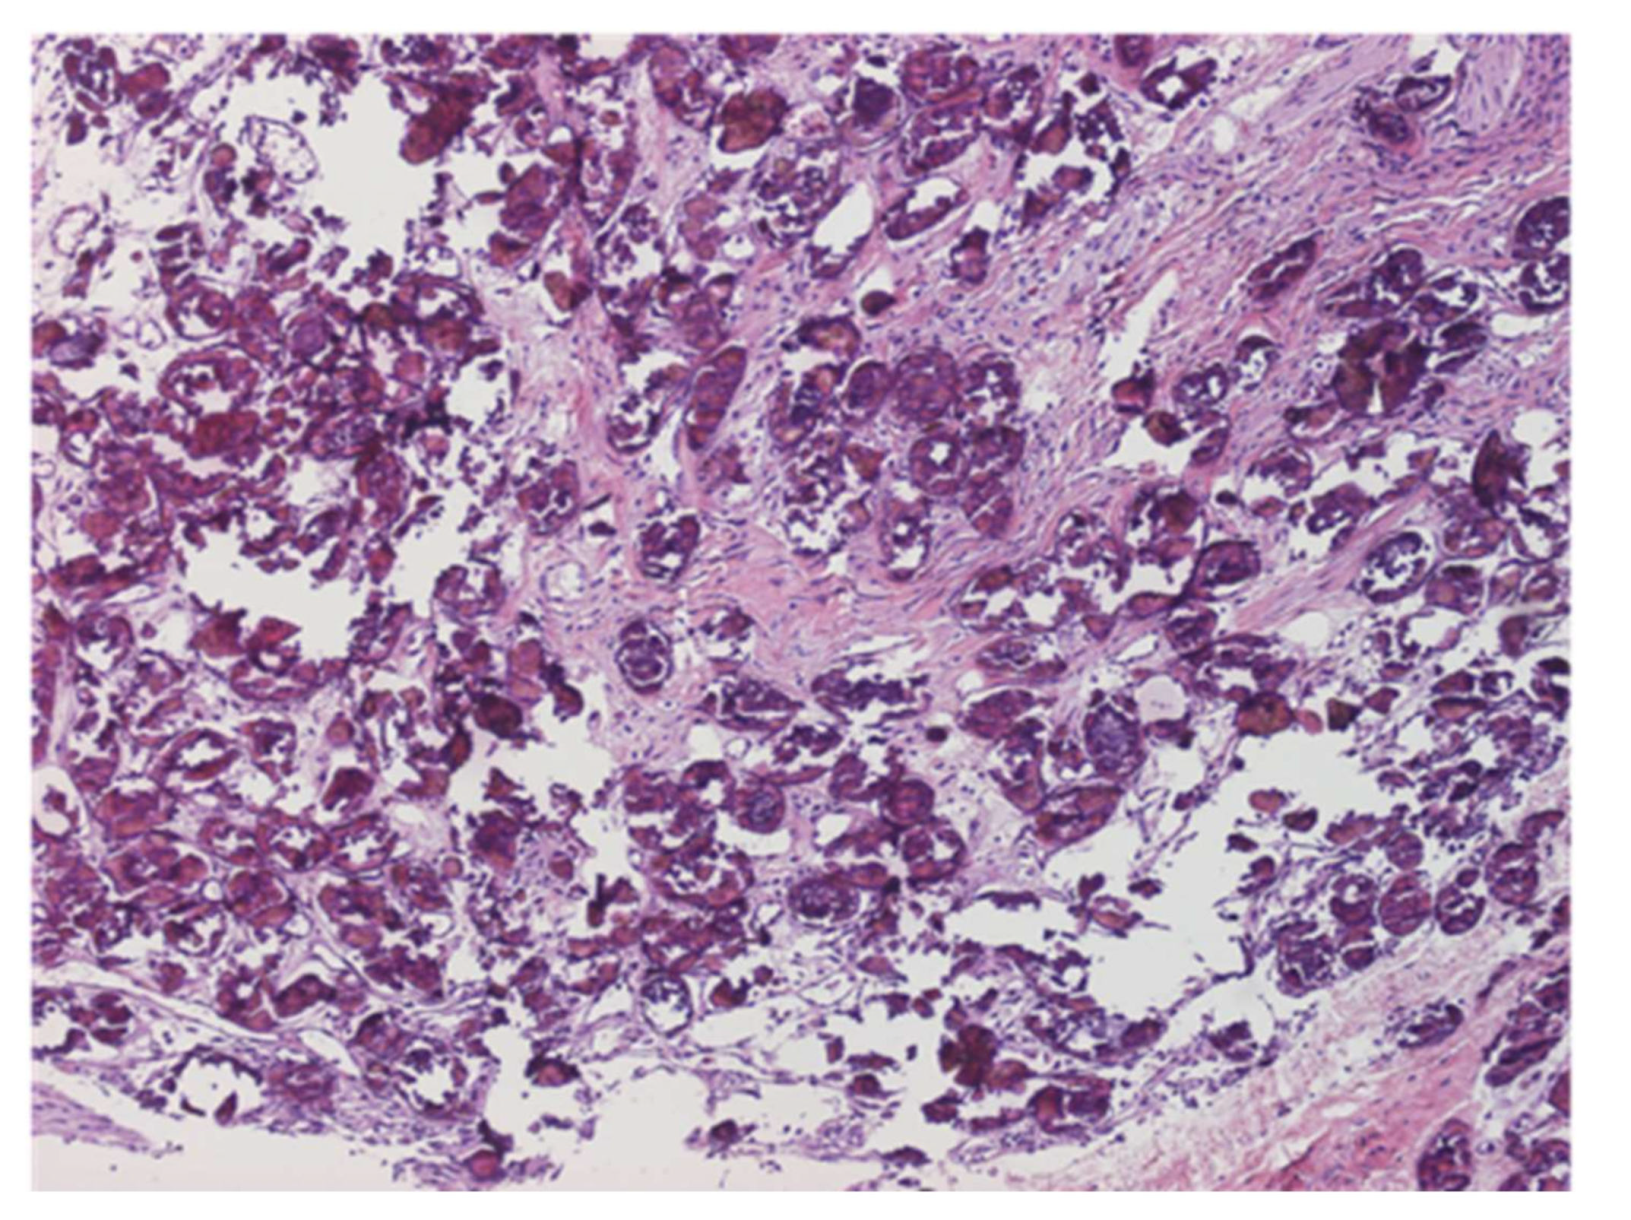

8. Urogenital Schistosomiasis

8.1. Urinary Schistosomiasis

- Barsoum, R.S. Urinary Schistosomiasis: Review. J. Adv. Res. 2013, 4, 453–459. [Google Scholar] [CrossRef] [PubMed] [Green Version]

- Salas-Coronas, J.; Vázquez-Villegas, J.; Soriano-Pérez, M.J.; Cabezas-Fernández, M.T. Esquistosomiasis urinaria. Med. Clín. 2014, 142, 281. [Google Scholar] [CrossRef]